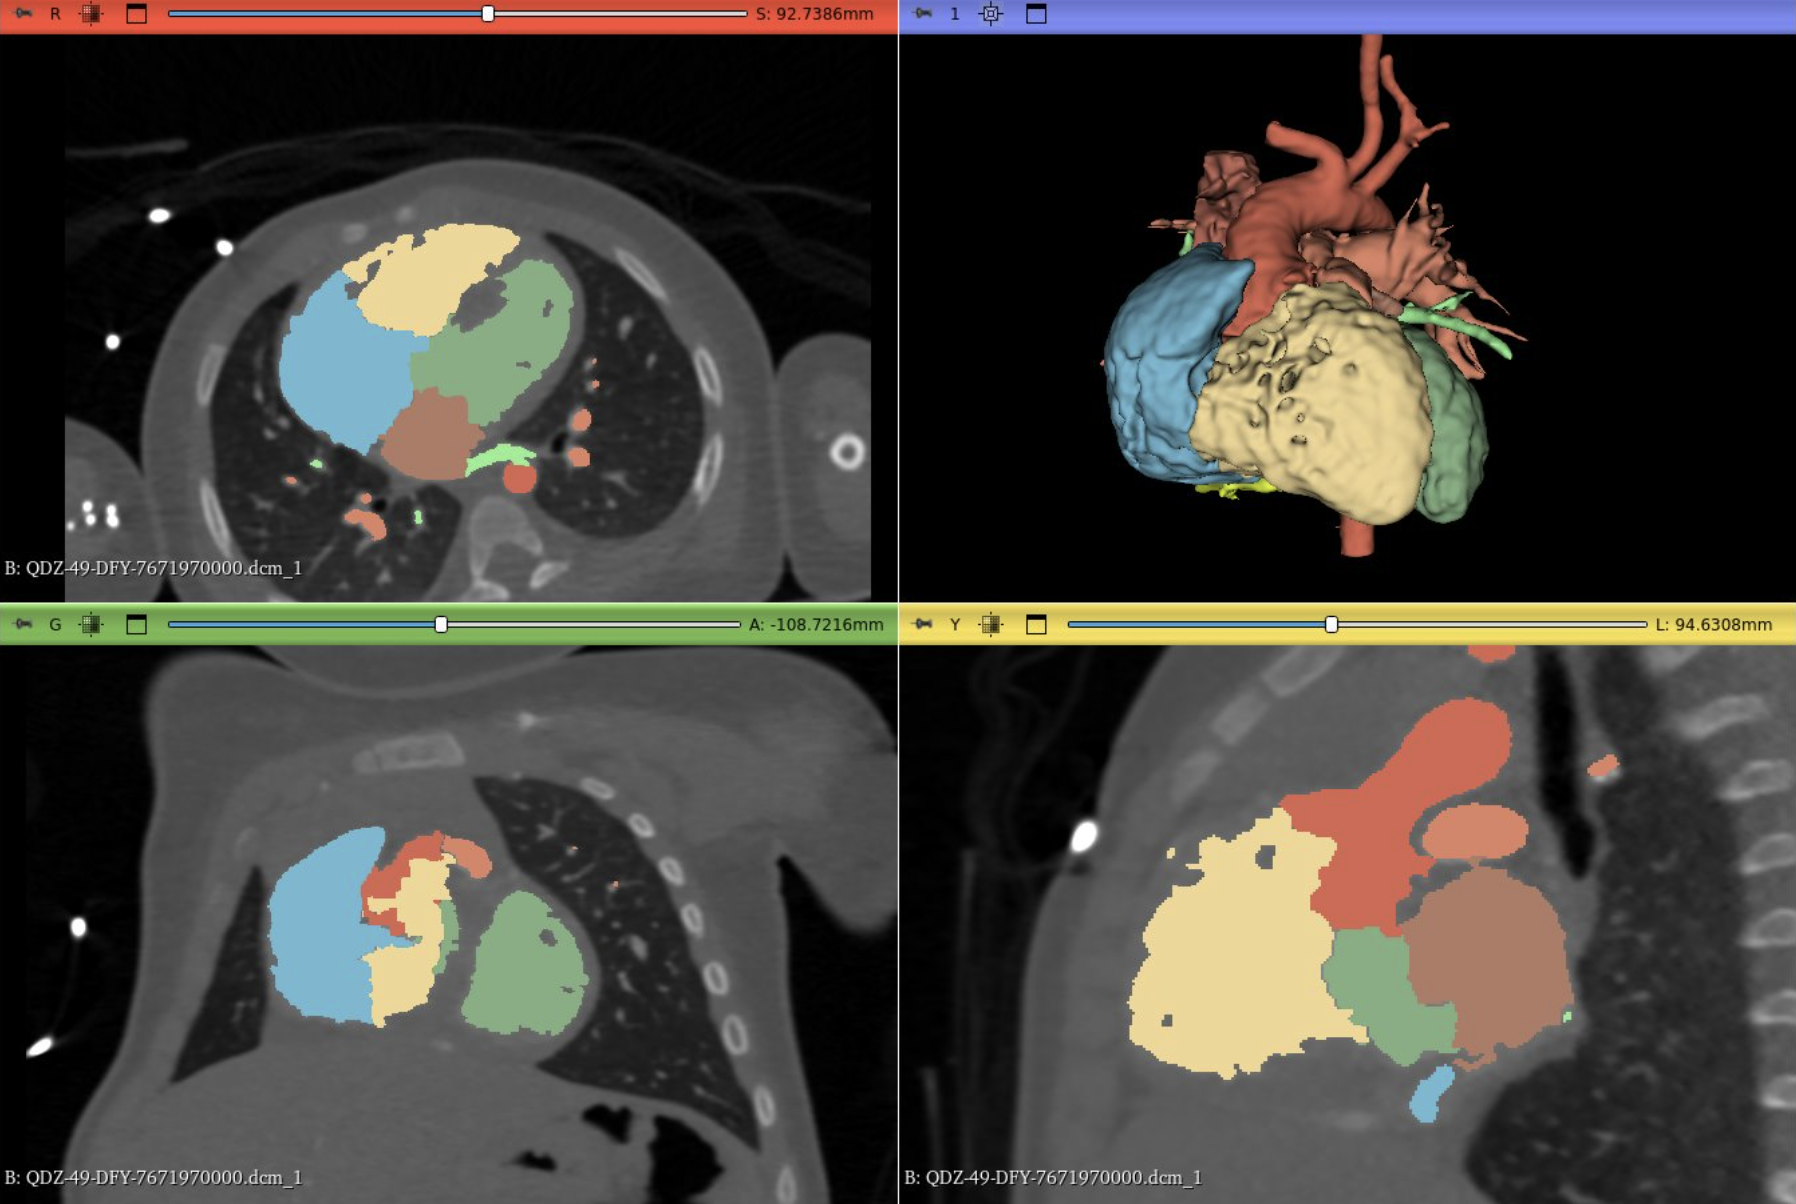

VR-Heart

3D heart visualization from CT for Congenital Heart Disease (CHD) and VR surgical consultations.

Addressed the challenge surgeons face in visualizing 2D scans as 3D structures for Congenital Heart Disease (CHD). The team used AI to automate the segmentation of the heart from CT scans (reducing manual time from 2–3 hours), allowing the heart models to be loaded into Virtual Reality for surgical consultations.

Whole heart segmentation

0.9 DICE score for whole heart segmentation (bloodpool).

Chamber and vessel segmentation

0.783 DICE score for chamber and vessel segmentation.

VR & 3D Lab

A VR and 3D Lab where surgeons perform VR consultations to gain confidence for complex surgeries.